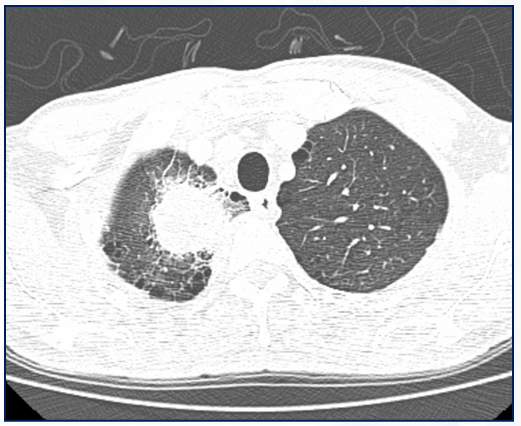

Quais os achados do Rx de tórax PA e perfil?

Hiperinsuflação pulmonar em paciente com quadro de exacerbação aguda de asma.

Hiperinsuflação transitória, apresentando

melhora após o tratamento do quadro agudo.